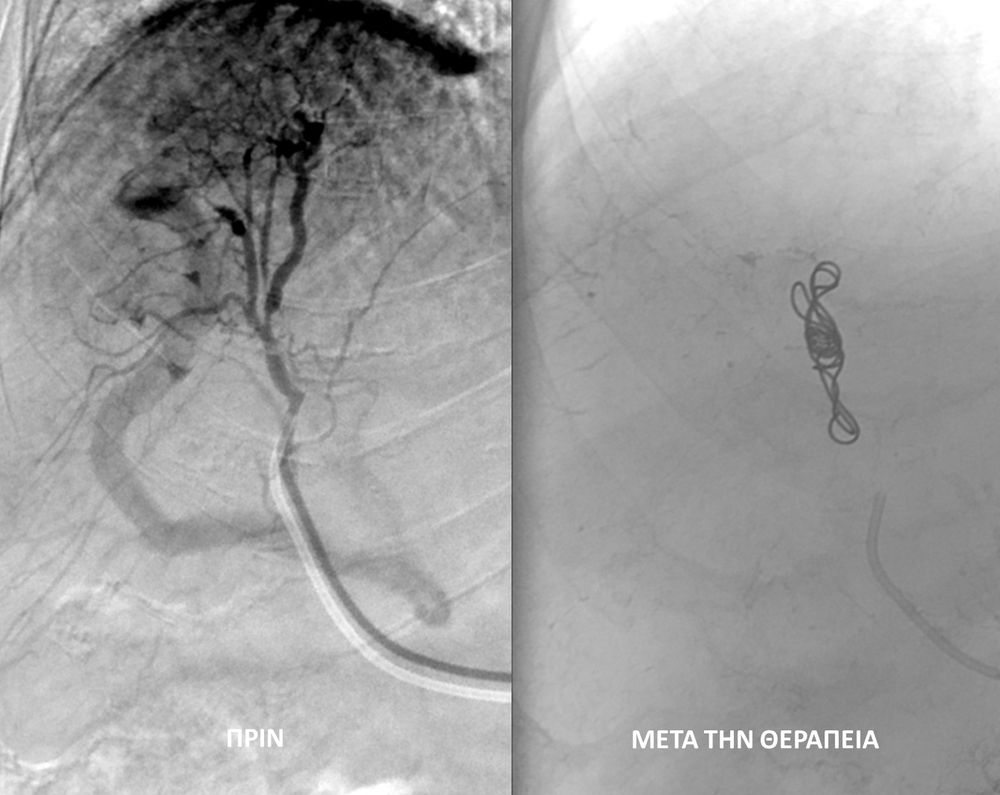

♦ Όγκους

Είτε προεγχειρητικά για την ελάττωση της αιμάτωσης του όγκου, είτε θεραπευτικά σε ορισμένες περιπτώσεις που δεν απαιτείται χειρουργείο ή υπάρχει αντενδειξη για χειρουργική αφαίρεση του όγκου.

Συνοπτικά υπό την καθοδήγηση του αγγειογράφου, αναγνωρίζεταιτο παθολογικό αγγείο-αγγεία και με ειδικούς καθετήρες και μικροκαθετήρες, διοχετεύονται εμβολικά υλικάόπως μικροσφαιρίδια ή coils, ώστε να αποφραχθεί ή να μειωθεί η παθολογική αγγείωση.